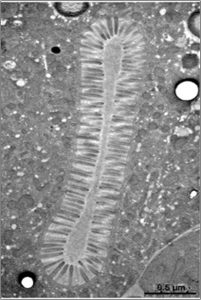

Electron micrograph showing damaged microvilli following bacterial infection in mouse intestine (Savkovic, S.D., et al. (2005).

We are using C. elegans as our model organism, which provides us with a robust genetic toolkit and features a simple intestine consisting of only 20 cells, each covered with microvilli. Moreover, we are using super resolution microscopy to understand the mechanisms behind the process, which could then be translated into human cell models and serve as a bedrock for the development of various treatments for microvilli-related intestinal diseases.